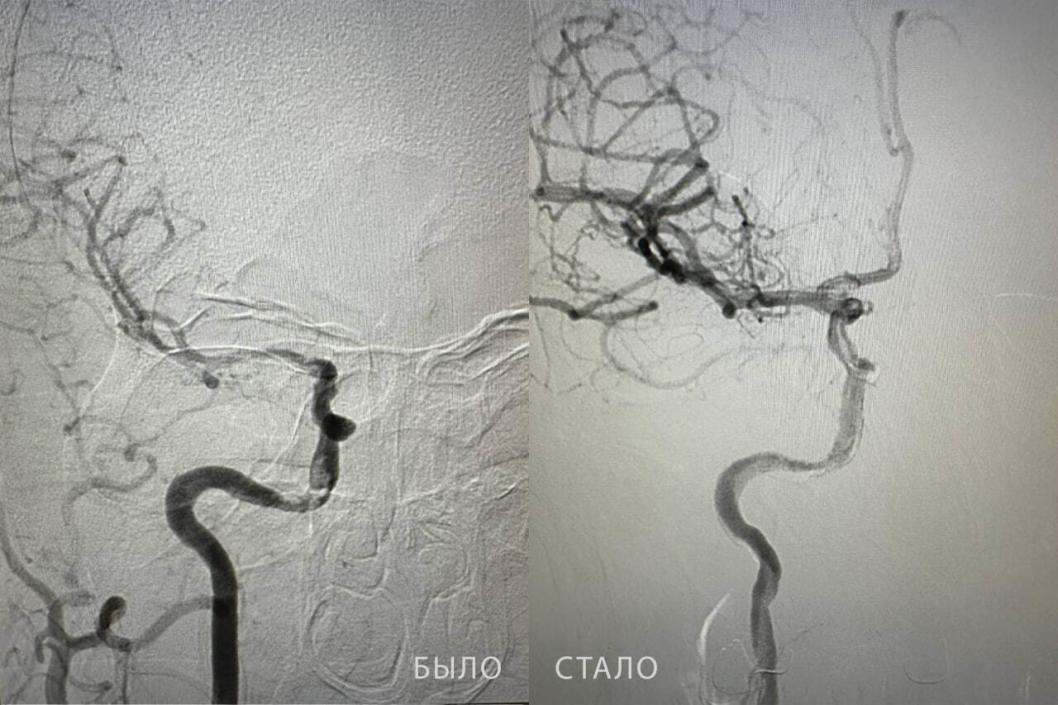

Тюменские врачи спасли молодого пациента от тяжелых последствий инсульта

У мужчины извлекли двухсантиметровый тромб

Пациент поступил медучреждение в тяжелом состоянии — с потерей сознания, судорогами, нарушением речи, асимметрией лица и отсутствием движений в левых конечностях. Во время исследования кровеносных сосудов врачи обнаружили тромб в правой внутренней сонной артерии.

– Ангиохирург Бакназар Абдыкадыров провел сложную операцию, которая длилась более получаса. Он извлек из сосуда тромб длиной почти два сантиметра. После высокотехнологичного вмешательства кровоток был полностью восстановлен, – рассказали в ведомстве.